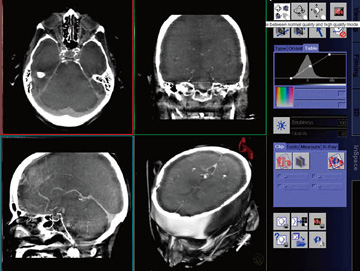

昨年のRSNA2004にて反響を巻き起こした最新の3Dイメージング機能である(図10)。ダイナミックレンジ特性に優れたFDは,Cアーム回転による三次元再構成画像においても高い密度分解能を有する。これに加え,CTに準ずる各種アーチファクト補正機能を搭載することで,10HU/10mmの密度分解能を実現した。このため,従来の血管系だけでなく,CTのような軟部組織の3DやMPR像の描出も可能になった(図11)。2004年11月より千葉県がんセンター様での運用が開始されたのに始まり,現在では国内の12施設(2005年8月時点)でお使いいただいており,今後も多くのご施設への設置が進行していく予定である。

図11 DynaCT画像例